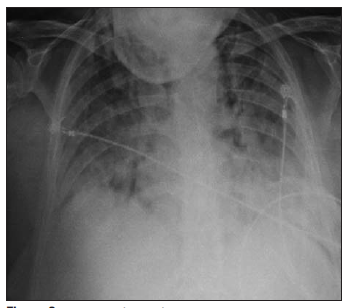

Se evidenciaron infiltrados bilaterales de los cuatro cuadrantes en la radiografía de tórax (Figura 2) y la tomografía de tórax mostró imágenes en vidrio deslustrado bilaterales con compromiso del espacio aéreo alveolar, con derrame pleural bilateral leve. Los sectores de hígado y bazo estudiados no mostraron alteraciones de su densidad.

Figura 2 Radiografía de tórax al ingreso a la unidad de cuidados intensivos (18/12/2014). Infiltrados bilaterales y difusos de los cuatro cuadrantes.